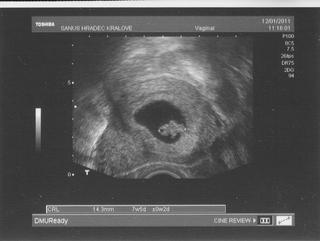

ahojky holky 🙂 omlouvam se ze vas tak napinam, ale kontrola u dr. dopadla dobre.. nebyl tam sice muj dr. ale dr. silhan, ale i tak to bylo fajn 🙂 Mimco je jedno a srdicko tam blikalo, i kdyz ho nepustil abysme ho slyseli... 25.1. jsme objednani na screening, takze uz ted mam nerviky zda bude vse OK 🙂 jinak fazolka ma 14,3mm a tady ji mate ve sve plne krase 🙂

Lenda.....fazolka je pěkná,taková fotogenická.Ty si se ségrou tak nějak stejně,né?